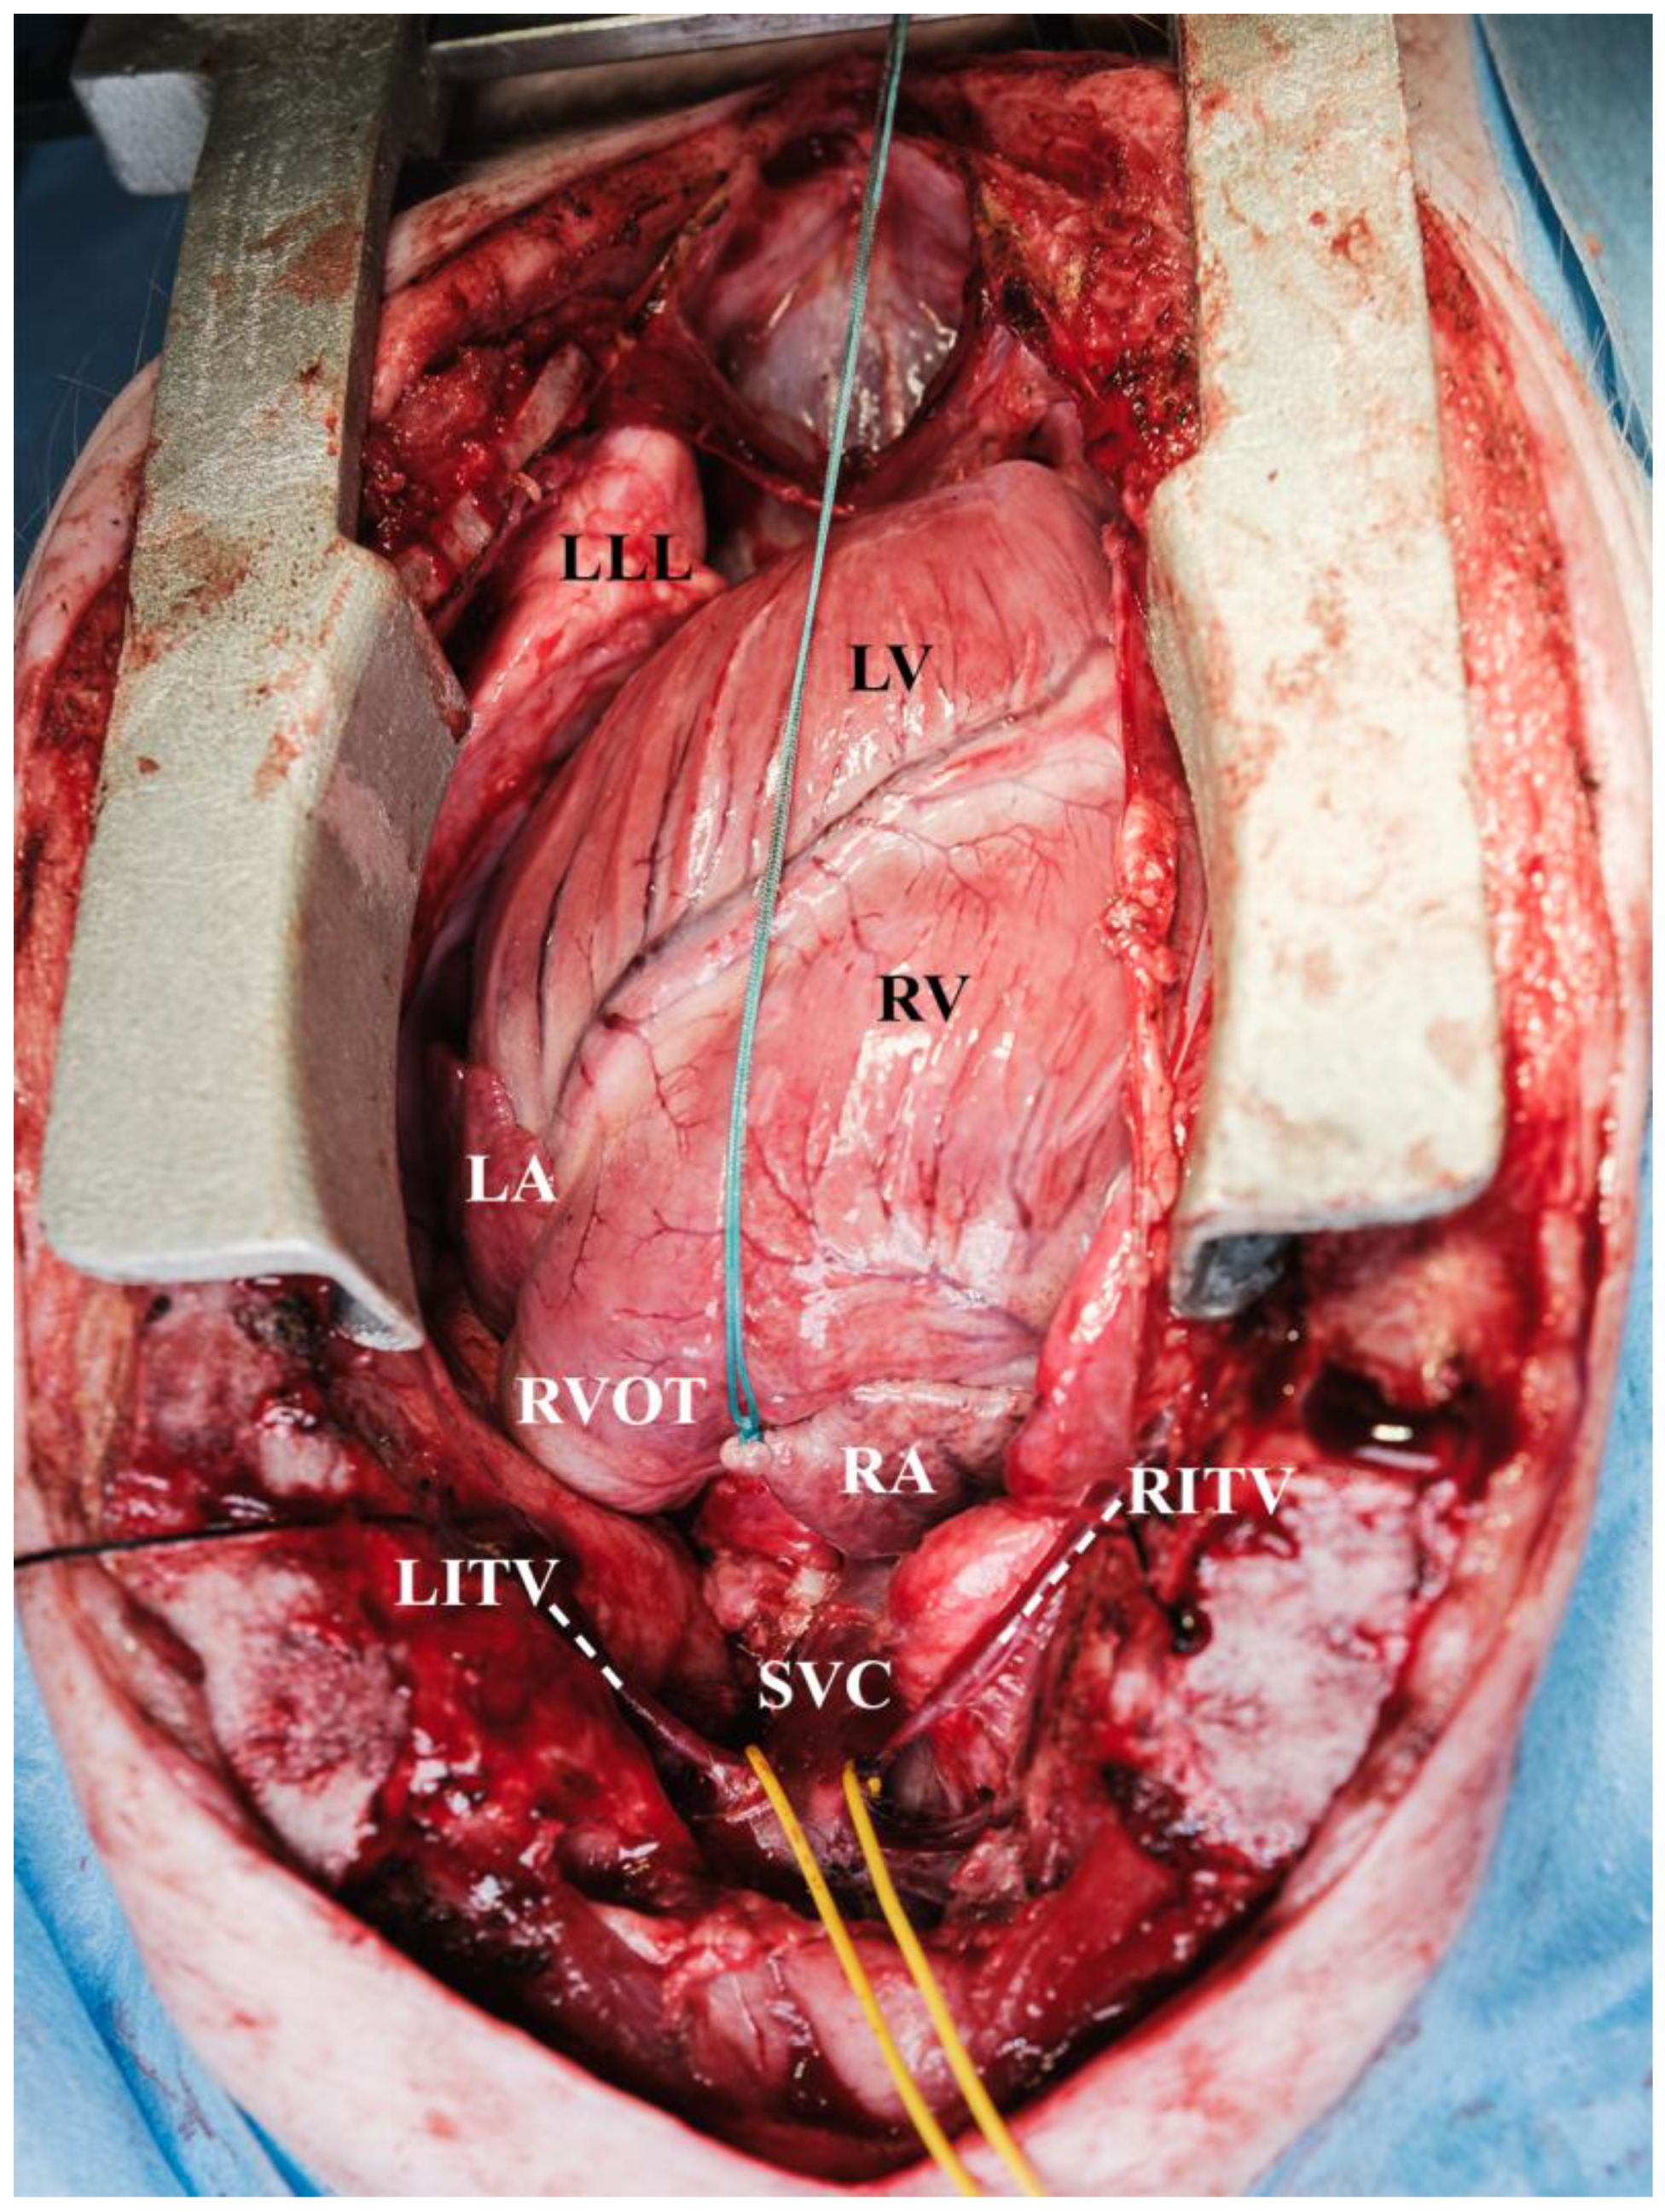

| LLL | left lower lobe |

| LV | left ventricle |

| RA | right atrium |

| RITV | right internal thoracic vein |

| RJV | right jugular vein |

| RV | right ventricle |

| RVOT | right ventricular outflow tract |

| SVC | superior vena cava |

| UDPCP | unidirectional cavopulmonary connection |

| LITV | left internal thoracic vein |